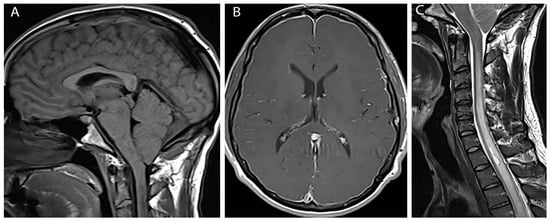

At three month follow up the patient reported modest improvement in headache symptoms. However, he had subsequently developed bilateral hand weakness and upper thoracic back pain. Physical exam was notable for bilateral finger flexor weakness, intrinsic hand muscle wasting, tongue fasciculations and ankle clonus. MRI of the brain and cervical cord with and without contrast revealed diffuse pachymeningeal enhancement, sagging brainstem, low lying cerebellar tonsils (10 mm descent) with crowding at the foramen magnum, and venous engorgement of the cervical epidural space (Figure 1A,B). This constellation of findings was suggestive of intracranial hypotension. Additionally, there was diffuse spinal cord signal abnormality involving cervical and upper thoracic spinal cord to the level of T8-T9 with a small syrinx at T1-T2 and an epidural fluid collection in the mid-thoracic spine (Figure 1C).

Figure 1. Pre-treatment images (A) Sagittal T1 weighted image shows herniation of cerebellar tonsils below foramen magnum; (B) Axial post gadolinium image shows diffuse pachymengeal enhancement; (C) Sagittal T2 weighted image shows extensive cord edema and syrinx.